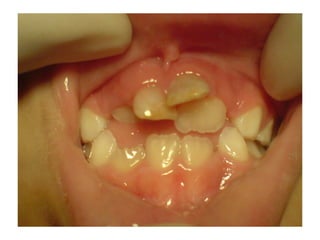

Τοπικοί παράγοντες

   Οδοντοφατνιακή λοίμωξη. Η μικροβιακής

αιτιολογίας φλεγμονή, διαχέεται μέσω του

οστού, στο σπέρμα του μόνιμου δοντιού,

προσβάλλοντας το αδαμαντινικό επιθήλιο

   Χρόνια αποστήματα νεογιλών γομφίων

προκαλούν βλάβη στους μόνιμους

προγόμφιους – συχνότητα 20- 25%

Οδοντικό τραύμα στα πρόσθια δόντια

 Όσο μικρότερο το παιδί, τόσο οι

πιθανότητες για βλάβη στο σπέρμα του

μόνιμου δοντιού είναι μεγαλύτερες

 Συχνότερα σε εμβυθίσεις, ολικές

εκγομφώσεις.